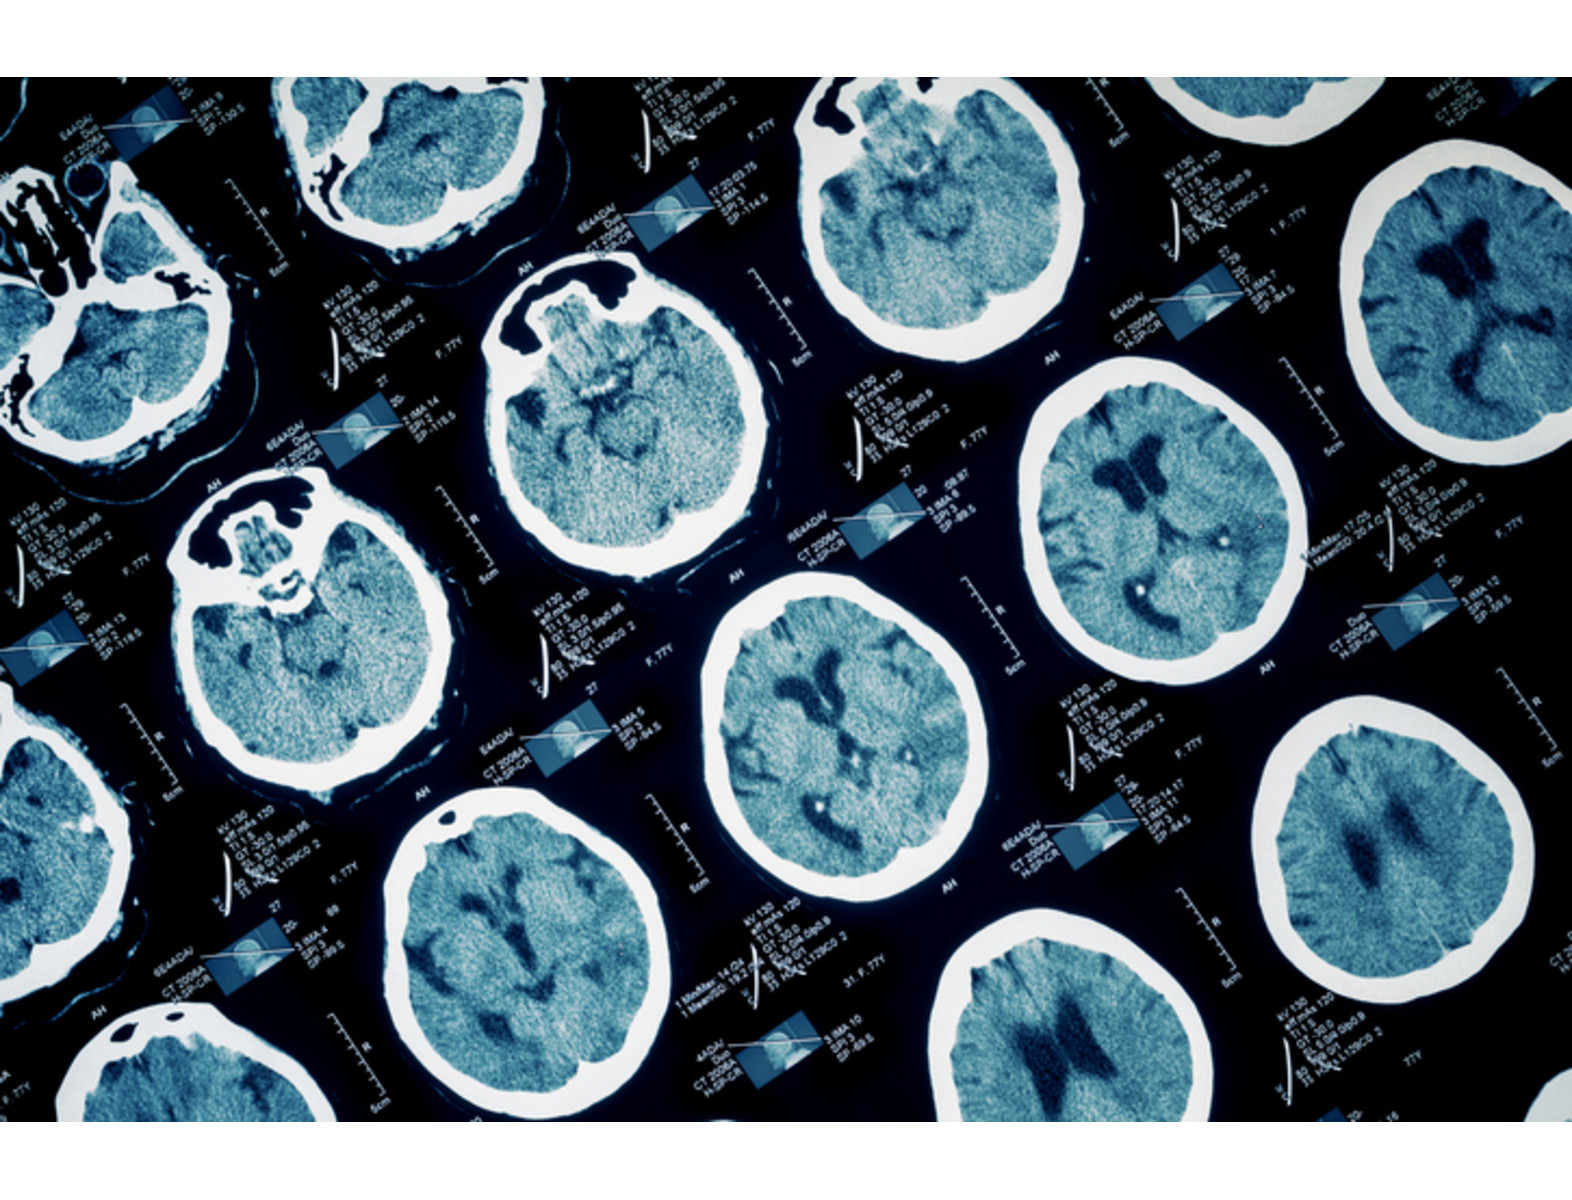

La epilepsia es un trastorno neurológico que afecta a más de 50 millones de personas en el mundo, y aproximadamente 3 millones en EE.UU. Sin embargo, especialistas advierten que hasta el 70% de las personas que la padecen pueden vivir sin convulsiones si recibieran un diagnóstico a tiempo y un tratamiento adecuado. Conoce aquí sus síntomas, causas y tratamientos.